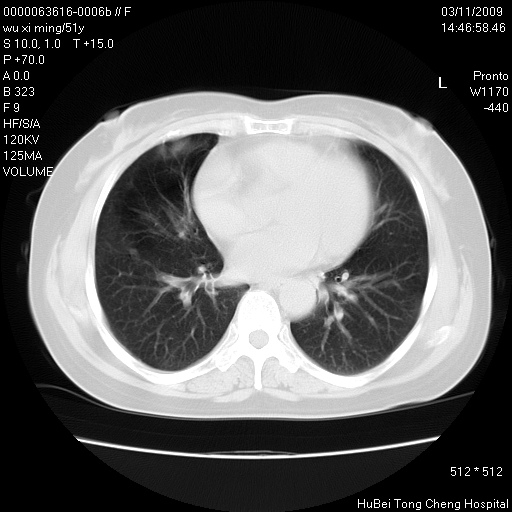

患者 女,51岁。因“胆囊炎,胆囊结石”,行常规术前胸部x线检查发现:右上肺结节病灶,建议行进一步检查。患者无咳嗽、咳痰及咯血等呼吸道症状,近期出现背部疼痛不适。

胸部ct轴位平扫(层厚10mm,螺距1.5,重建间隔10mm;部分层面:层厚3mm,螺距1.0,重建间隔3mm),图像如下:

1、周围型肺癌。(毛刺正、血管束集征,分叶。)

集束征,胸膜牽拉征,毛刺,淺分葉高度提示ca.